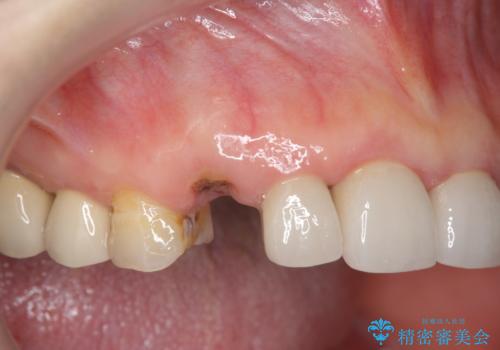

折れてしまった前歯 インプラントによる補綴治療